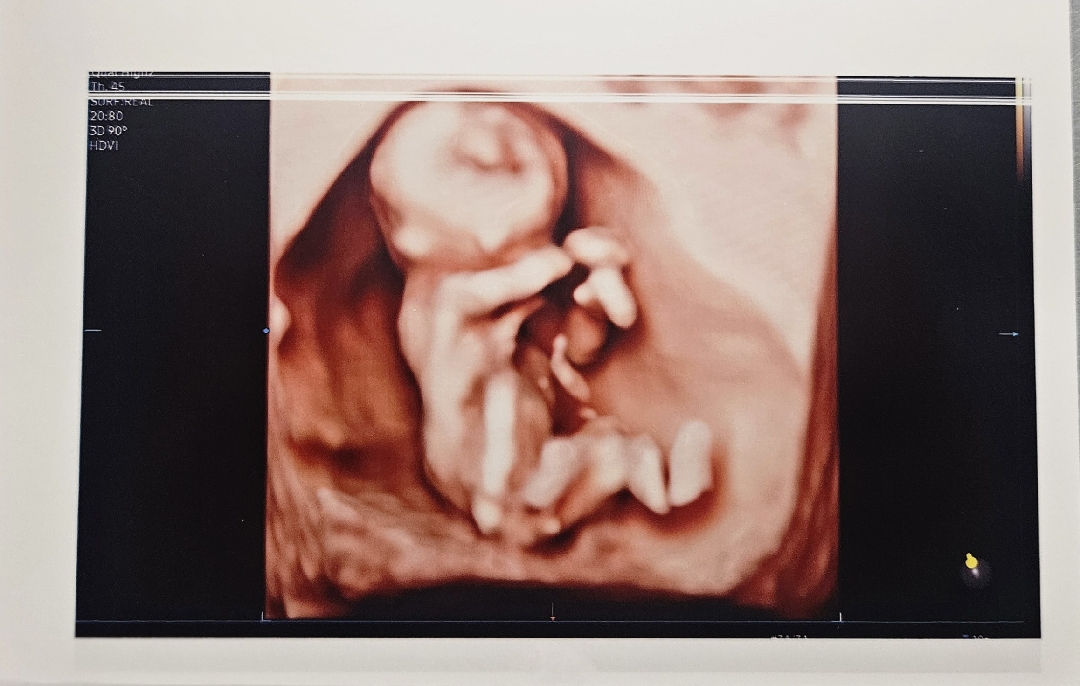

12주4일차 입체초음파 성별

혹시 이 사진 성별이 어떻게 보이시나요??남편은 딸이라그러고 제눈에는 아들로 보이네요ㅎㅎ병원에서는 아직 모른다는데 너무너무 궁금해서 투표 올려봅니다!!